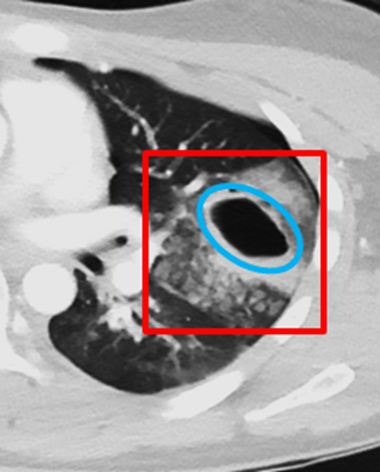

This patient demonstrates multiple acute findings consistent with those seen on the initial chest radiograph, including left-sided multiple rib fractures and a left pneumothorax. Given the mechanism of acute blunt trauma and the associated rib fractures, the areas of consolidation are most consistent with pulmonary contusions. Axial CT images reveal air- and fluid-filled cystic structures in the posterior aspects of both lungs, consistent with traumatic pneumohematoceles. Additionally, subcutaneous emphysema is visualized along the left chest wall on axial sections.

In the setting of high-energy trauma, pulmonary lacerations should be strongly considered. These occur due to rupture of the alveolar walls and surrounding lung parenchyma, creating cavities filled with air (pneumatocele), blood (hematoma), or both (pneumohematocele). In this case, bilateral pulmonary lacerations are evident: on the right, likely due to shear forces against the vertebral bodies; and on the left, likely due to direct puncture from fractured ribs—together forming a classic pattern. Subsequent development of traumatic pneumohematoceles is observed.

There are displaced, comminuted, and non-displaced fractures of the left 5th through 8th ribs. Associated findings include subcutaneous emphysema within the left chest wall, a left-sided hemopneumothorax, and bilateral pulmonary contusions. Multiple bilateral post-traumatic pneumatoceles containing air-fluid levels are noted, with the left-sided lesion showing perilesional hemorrhage, suggesting a traumatic etiology.